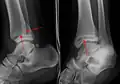

AP manual stress view showing a deltoid ligament tear

A specialized AP stress view of the ankle is performed when there is concern for an unstable ankle injury. There are two types of stress views: gravity and mechanical.[11] In the gravity stress view, the patient lies in the lateral decubitus position with the ankle dangling over the edge of the table to mimic the mechanical stress view.